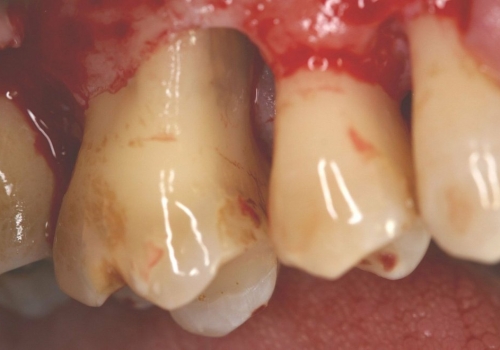

Qeyri-cərrahi parodontoloji müalicədən sonra bəzi hallarda, bu və ya digər bölgədə dərin parodontal ciblər (diş əti və sümük cibi) qalmaqda davam edir. Bu hallarda çox zaman müalicə cərrahi metodların tətbiqi ilə davam etdirilir. Bu zaman əsas məqsəd mövcud parodontal cibin bu və ya digər metodlarda aradan qaldırılmasını təmin etməkdir.

Çünki bu ciblər çox zaman pasiyent tərəfindən yetərincə təmizlənə bilmir. Bu isə həmin bölgəyə tədricən ərp və dolayısı ilə də bakteriya koloniyalarının toplanmasına səbəb olur. Bu proses yenidən yerli iltihabın ortaya çıxmasına səbəb olur. Tətbiq edilən cərrahi metodlar əsasən cibin yerləşdiyi diş bölgəsi, cibin eni, dərinliyi, konfiqurasiyası və s. xüsusiyyətlərə görə müəyyənləşdirilir. Bu zaman məqsəd mümkün olduqda həmin bölgədə bərpa prosedurunu həyata keçirmək, mümkün olmadıqda isə rezektiv müalicənin tətbiqi ilə həmin bölgəyə ərp toplanma ehtimalını azaltmaq və gigiyenik prosedurların icrasını pasiyent üçün rahatlaşdırmaqdır.

Rezektiv prosedurlar zamanı müəyyən miqdarda yumuşaq toxuma (diş əti), sərt toxuma (sümük) və ya kombinə olunmuş şəkildə (həm sümük, həm də yumuşaq toxuma) rezeksiya həyata keçirilir. Prosedur yerli ağrısızlaşdırma altında aparılır. Əməliyyatdan sonrakı dövrdə fərdi qulluq və gigiyena qaydalarının mötəxəssis tərəfindən izahı və müvafiq instruksiyanın verilməsi olduqca önəmlidir.